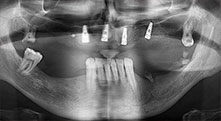

Un paciente de 40 años con una dentadura restante desastrosa desea someterse a un tratamiento mediante implantes. Como es fumador, en el maxilar superior no se planea una elevación del seno con prótesis dental fija, sino una prótesis mediante puente sobre cuatro implantes anteriores.

Piezomed B6

La cresta alveolar se ranura en ambos lados mediante piezocirugía (inserto: Piezomed B6). La implantación se realiza en la misma intervención y el hueso que rodea el implante se estructura además con una regeneración ósea guiada (GBR).

Implantes

Los cuatro implantes se encuentran in situ tal como estaba planeado. Los molares distales del maxilar superior sirven además para fijar la prótesis con base reconstruida, que se monta un mes después de la implantación.